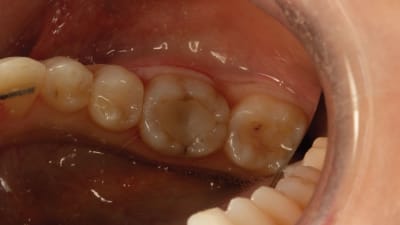

Clinical Briefs Restorative Indirect Materials Treating a Fractured Molar By Daniel Vasquez, DDS November 01, 2023 6 min read